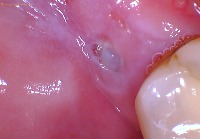

Here is another intraoral photo from a different patient where you can see a hole in the gums behind the molar. That is where the third molar is trying to come in.